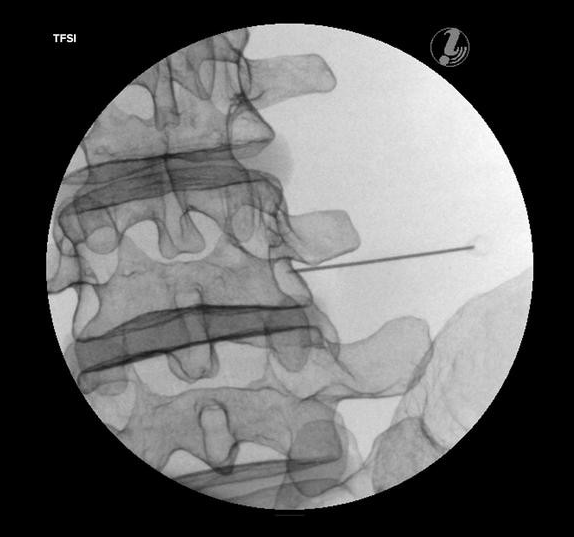

TRENAŻER DO ZNIECZULANIA ZEWNĄTRZOPONOWEGO W ODCINKU LĘDŹWIOWYM POD KONTROLĄ USG

Trenażer do znieczulania zewnątrzoponowego w odcinku lędźwiowym pod kontrolą USG umożliwia naukę diagnozowania źródła bólu, identyfikacji tkanki docelowej i narażonych struktur, przy użyciu USG i anatomicznych punktów.

Przy użyciu symulatora można przeprowadzać m.in:

• znieczulenie zewnątrzoponowe TFSI

• blokadę gałęzi podstawnej-przyśrodkowej

• blokadę stawu krzyżowo-biodrowego